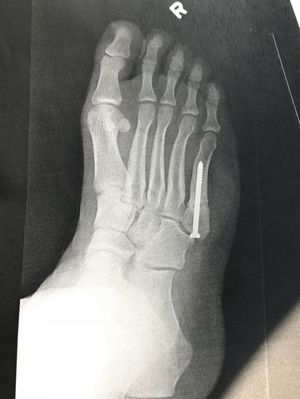

5th metatarsal repair surgery, post op 4 months

A follow up to a previously posted surgery, which can be seen, along with other X-ray angles on my profile

Jones fracture?

Yes sir